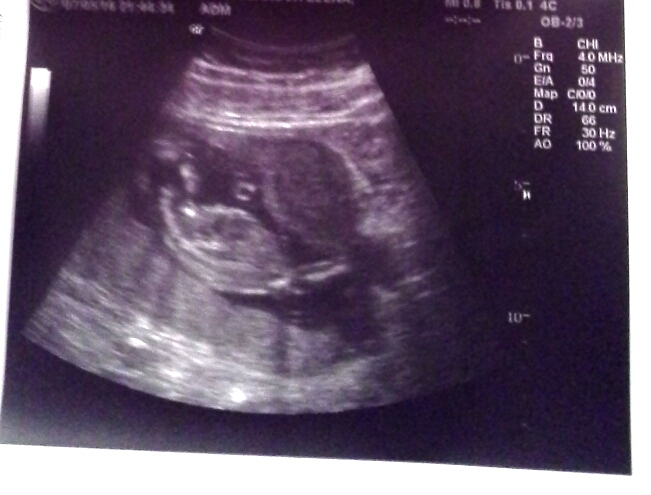

Домовёшка молодец,живой,"крутится-вертится шар голубой",весит 156 гр и вымахал до 14 см,писюньку не показывает.

Повезло с дежурными гинекологами,всё быстренько организовали,поймали спазм(это выпячивание матки напротив живота дитёнка),сфоткали и подарили снимки.

Тонус на узи всегда очень хорошо виден, причем невооруженным глазом. А вообще он не так страшен, если его правильно лечить. Вот здесь рассказано почему появляется тонус, как он лечится на разных сроках, как его не провоцировать и как ускорить его лечение. Берегите себя и своего малыша